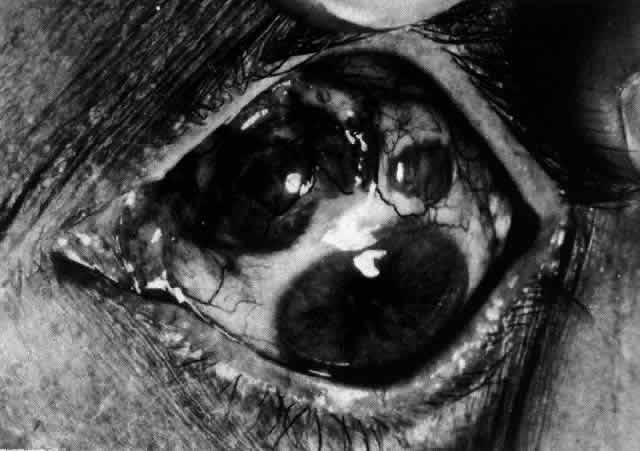

The sclera that is edematous is pushed forward, and the deep episcleral network is more congested than the superficial networks (Figs. 27 and 28). It is usually easy to ascertain by simple observation that the patient has scleritis and not episcleritis. However, it is not as easy to ascertain whether the patient has early necrotizing scleritis. It is in these patients that fluorescein angiography has considerable value, because the first changes are detectable in the ocular vasculature. Prompt and adequate treatment can prevent these changes from becoming irreversible.

Fig. 27. In scleritis, maximum congestion occurs in deep episcleral plexus, which is bowed forward by underlying scleral edema. Episcleral tissue is slightly infiltrated and superficial plexus is slightly congested (see Fig. 14). (Watson PG, Hayreh S, Awdry P: Episcleritis and scleritis. Br J Ophthalmol 52:278–279, 1968)

Fig. 28. Nodular scleritis. Both the anterior conjunctival slit and the deep scleral slit are displaced forward by the scleral edema. There is little separation between these two beams, indicating that all the edema is in the sclera and not in the overlying episclera. (Watson PG, Hayreh S, Awdry P: Episcleritis and scleritis. Br J Ophthalmol 52:278–279, 1968)